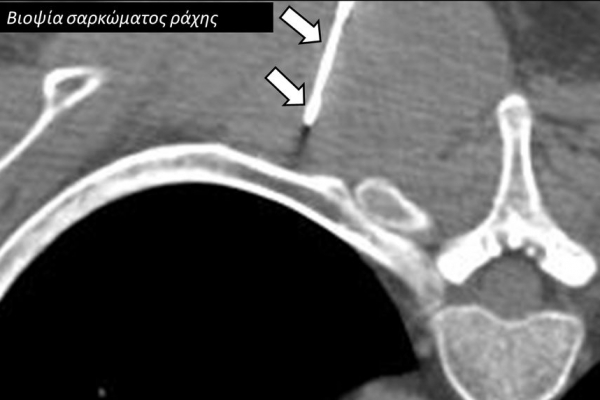

Η διαδερμική βιοψία είναι μία ελάχιστα επεμβατική μέθοδος λήψης υλικού από τον όγκο για κυτταρολογική και ιστολογική εξέταση, από εστιακές αλλοιώσεις του ήπατος, πνεύμονα, νεφρού κλπ. Συστήνεται από τον κλινικό ιατρό ανάλογα με το είδος και το μέγεθος της βλάβης και πραγματοποιείται με ασφάλεια από επεμβατικό ακτινολόγο με την καθοδήγηση αξονικού τομογράφου ή υπερήχων. Στη σύγχρονη ογκολογική θεραπεία όπου γίνεται προσπάθεια καταπολέμησης του καρκίνου σε μοριακό επίπεδο κρίνεται αναγκαία η ακριβής ιστολογική ταυτοποίηση του όγκου ώστε να εφαρμοσθεί εξατομικευμένη θεραπεία για το βέλτιστο αποτέλεσμα. Οι κατευθυνόμενες βιοψίες στοχευουν στο να παρέχουν στον κλινικό ογκολόγο το απαραίτο ιστοπαθολογικό υλικό που θα του επιτρέψει να εφαρμόσει την κατάλληλη θεραπεία για τον ογκολογικό ασθενή.